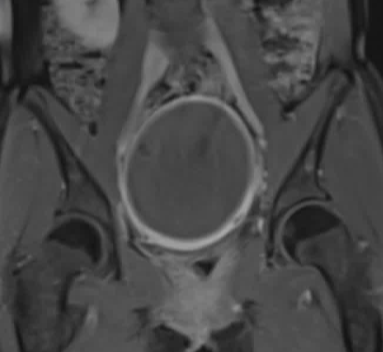

47 岁的 G1P1 女性因持续两年的月经过多症状前来就诊。 症状还包括盆腔痉挛性疼痛、尿频和背痛。妇科病史显示存在一种已知的苗勒管异常(MDA)。按照方案要求进行了盆腔磁共振成像(MR)检查,以评估子宫肌瘤栓塞术(UFE)的情况。检查结果显示为单角子宫,其主导的右侧子宫角存在强化的全层和黏膜下肌瘤,左侧则有一个相通的原始子宫角。 MR 还显示右侧有一个孤立的肾脏,右侧子宫动脉占主导地位,而左侧的子宫动脉和卵巢动脉均无法辨认。 子宫肌瘤被认为是导致月经过多和下腹肿块症状的原因。

手术通过左侧桡动脉路径进行。 动脉造影显示右侧肾脏为单侧,右侧子宫动脉为单支,且左侧未发育的子宫角未获得明显的动脉供血。 通过一根微导管,使用直径为 500 - 700 微米的标定微球对右侧子宫动脉进行了栓塞,直至达到“修剪后的树状”终点位置。患者当天就出院了。 在三个月的随访中,患者表示所有症状都有所改善。

一例罕见的单角子宫伴症状性肌瘤病例,该病例通过子宫动脉栓塞术(UFE)得到了成功治疗。 在这种情况下,单独的一侧子宫动脉被进行了栓塞处理,取得了良好的临床效果,并没有发生不完全坏死。 虽然有关单侧子宫动脉栓塞术的疗效和效果的研究已有相关报道,但目前尚未有关于单动脉供血子宫肌瘤患者接受 UFE 手术的任何研究报道,此病例证实在左侧子宫动脉缺如的情况下,单纯栓塞右侧子宫动脉也可以达到完全坏死的情况。 1.Walker WJ, McDowell SJ. Pregnancy after uterine artery embolization for leiomyomata: a series of 56 completed pregnancies. Am J Obstet Gynecol. 2006 Nov;195(5):1266-71 | ||||||||||||||||||||||||